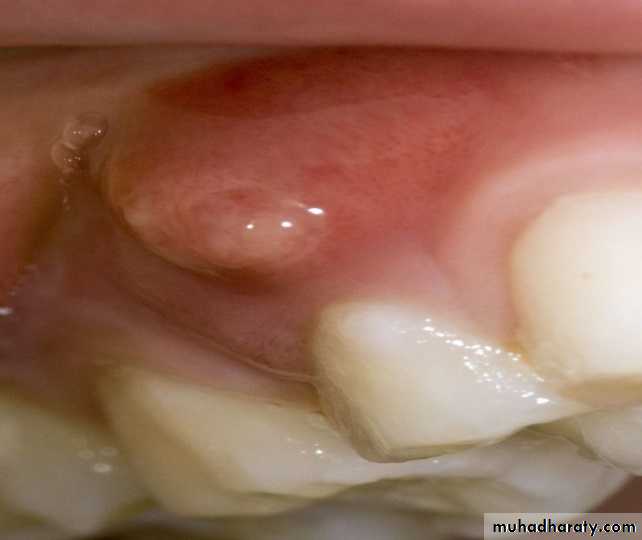

Sinus tract I.O

Sinus tract : is a tract leading from enclosed area of infection to an epithelial surface .

It is usually associated with chronic P.A abscess in general, although in acute exacerbation of chronic abscess is also observed (pheonix abscecss) .